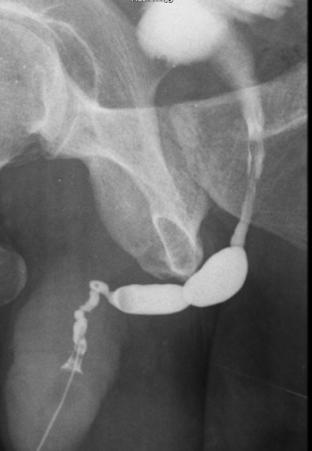

Imagem de Estenose Uretral

Uretrografia mostrando uma estenose severa no segmento da uretra bulbar.